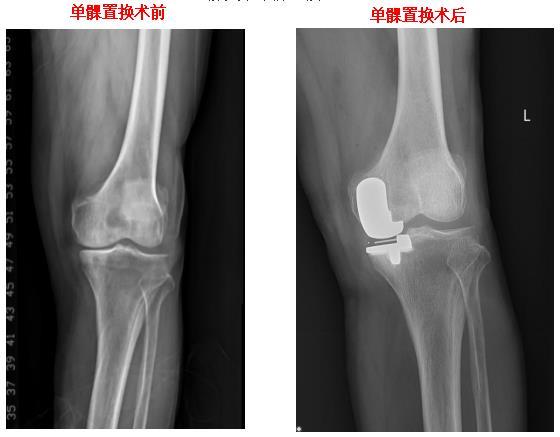

膝关节单髁置换

HTO截骨矫正膝关节内翻畸形

膝关节表面置换